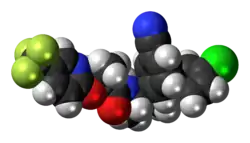

| 3D model (JSmol) | |

Taranabant (codenamed MK-0364) is a cannabinoid receptor type 1 (CB1) inverse agonist that was investigated as a potential treatment for obesity due to its anorectic effects.[1][2] It was discovered by Merck & Co.

- ↑ Fong TM, Guan XM, Marsh DJ, Shen CP, Stribling DS, Rosko KM, et al. (Jun 2007). "Antiobesity efficacy of a novel cannabinoid-1 receptor inverse agonist, N-[(1S,2S)-3-(4-chlorophenyl)-2-(3-cyanophenyl)-1-methylpropyl]-2-methyl-2-5-(trifluoromethyl)pyridin-2-yl]oxy]propanamide (MK-0364), in rodents". Journal of Pharmacology and Experimental Therapeutics. 321 (3): 1013–22. doi:10.1124/jpet.106.118737. PMID 17327489. S2CID 20001781.